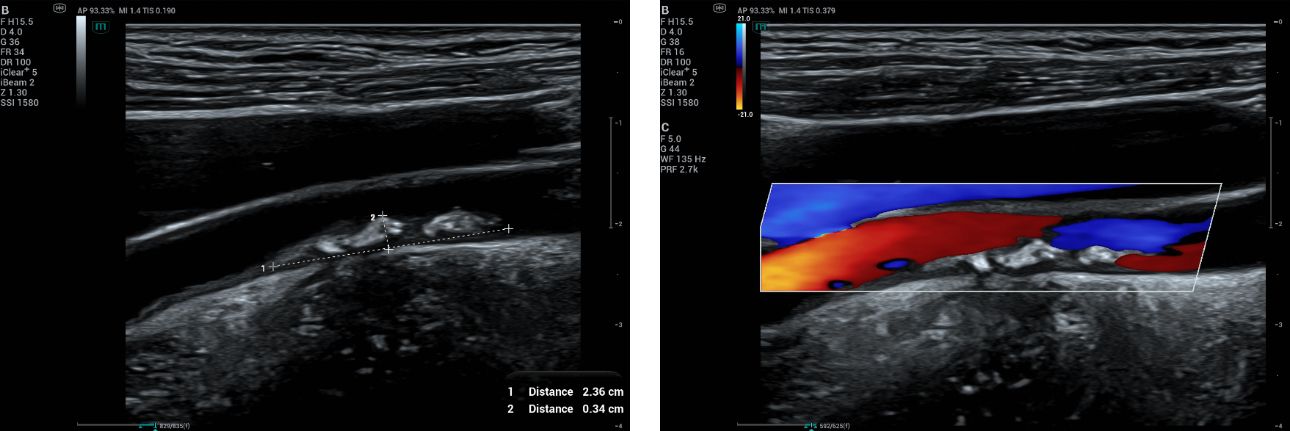

A 50-year-old female came for health screening with no symptoms. Carotid ultrasound assessment was done bilaterally. A plaque measuring 2.36 x 0.34 cm (Figure 1) was found on the right distal CCA.

Color Doppler is a standard tool to assess stenosis and overall flow. CF shown reversal flow at the stenosed area (Fig 2).

B mode and CF images of the right carotid plaque.

Fig.1 and 2: B mode and CF images of the right carotid plaque.

Area-based measurement using cross-sectional imaging (Fig 4), the area of the residual lumen can be directly measured. This method can more accurately quantify stenosis in plaques that are irregularly shaped and asymmetric in cross-sectional images. However, the non-linear relationship between diameter and area (A=πr2) means that the area method can yield higher percentages of stenosis than the diameter method.

Measuring percentage of stenosis using area-based method. This method manually trace the full vessel lumen and patented lumen in axial plane.

Fig.4: Measuring percentage of stenosis using area-based method. This method manually trace the full vessel lumen and patented lumen in axial plane.